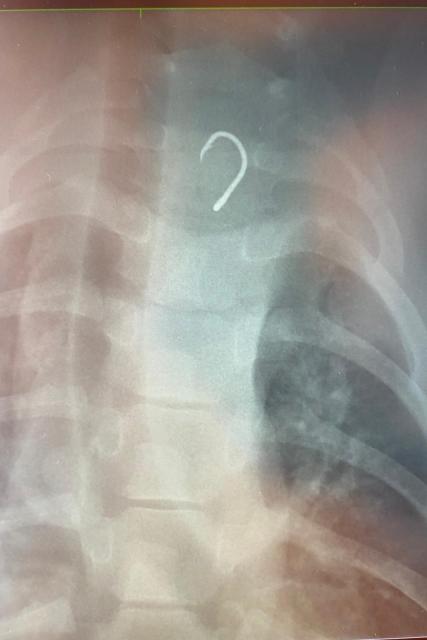

The Marine Mammal Center’s veterinary team took X-rays and confirmed that a fishing hook was lodged in the seal’s esophagus. The center’s team used special dehooking tools to safely remove the ingested hook while RS10 was under anesthesia.